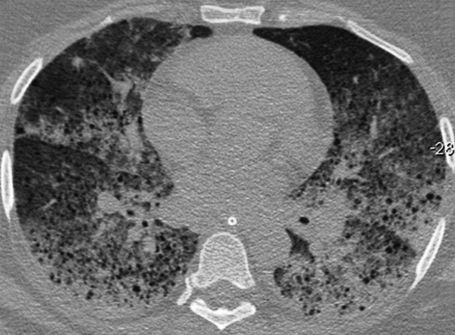

Thoracic computed tomography demonstrated bilateral and diffuse ground-glass attenuation opacities, which were predominant in the lower lobes of the lungs, and thin-walled cysts (Figure 1). A bronchoscopic examination revealed a moderate amount of blood in the segments of both lungs, and the lavage aliquots were progressively more hemorrhagic, which was consistent with the diagnosis of diffuse alveolar hemorrhage. The patient developed hemodynamic instability that resulted in the patient's death.